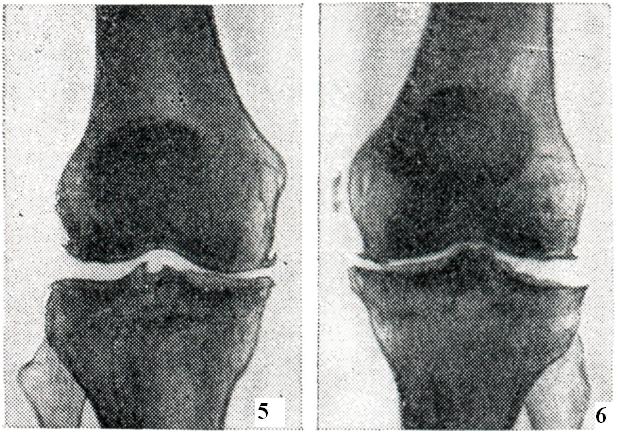

В субхондральных отделах отмечаются явления лакунарной резорбции и новообразования кости, а в зонах костных «шлифов» развивается остеосклероз. В более глубоких отделах эпифиза преобладает остеопороз с образованием кист, окруженных поясом склерозированной кости. Здесь же встречаются островки хрящевой ткани, которые, по мнению некоторых авторов, представляют собой разрастания хрящевой мозоли, распространяющейся из глубоких отделов необызвествленной зоны суставного хряща. В редких случаях островки хрящевой ткани в виде своеобразных «грыж» выбухают над поверхностью костных шлифов (рис. 4). Фиброзные и костные анктшозы при деформирующем артрозе, в отличие от артритов, не развиваются. Любой артроз развивается и протекает очень медленно и никогда не приводит к тяжелым нарушениям функции суставов и особенно к фиброзному и костному анкилозу. Исключением является тазо-бедренный сустав, отличающийся своими анатомическими особенностями (глубокая суставная яма, вмещающая около 2/3 головки бедренной кости, и сравнительно узкая суставная щель, быстро уменьшающаяся при любом патологическом процессе). В этом суставе очень рано наблюдается ограничение подвижности и вовлечение в процесс мышечно-связочных элементов, что в далеко зашедших случаях нередко является причиной инвалидизации больных. Однако анкилоз и в данном случае не наступает, если к артрозу не присоединяется воспалительный процесс. Любая форма артроза протекает без общих признаков воспаления (ускорение РОЭ, диспротеинемия, повышение температуры, исхудание и другого). Первичный артроз часто сопровождается нарушением жирового обмена, артериальной гипертензией, атеросклерозом и другими заболеваниями. Очень важной чертой артроза является несоответствие между морфологическими изменениями в суставах, наблюдаемыми на рентгенограммах, и клиническими проявлениями болезни. Иногда при незначительных рентгенологических изменениях отмечаются сильные боли и ограничение подвижности. В других случаях при значительных рентгенологических изменениях клинические симптомы оказываются весьма умеренными. Это зависит от нескольких причин. Во-первых, суставной хрящ полностью лишен сосудов и нервов. Поэтому его поражение не дает симптомов до тех пор, пока патологический процесс не выходит за пределы самого хряща. Во-вторых, синовиальная мембрана, суставная капсула, сухожилия и мышцы, имеющие многочисленные нервные рецепторы, воспринимающие боль, не во всех суставах поражаются в одно и то же время и в той же степени. В-третьих, не у всех больных артрозом развивается одинаково быстро: чем медленнее он начинается и протекает, тем менее выражены клинические симптомы, так как организм успевает использовать все компенсаторные приспособления. Суставные симптомы артроза складываются из болей, чувства скованности, быстрого утомления, тугоподвижности, деформаций, хруста и другого. Боли обычно тупые. Они непостоянны, усиливаются в холодную и сырую погоду, после длительной нагрузки (например, к вечеру) и при начальных движениях после состояния покоя («стартовые боли»). В тазо-бедренных суставах боли иррадиируют в паховую либо седалищную область (при этом отмечается напряжение отводящих мышц и сгибателей бедра). Очень часто, особенно при старческих артрозах, вместо болей отмечается лишь ломота и чувство тяжести в костях и суставах. Это ощущение весьма близко к чувству скованности при ревматоидном артрите, но отличается кратковременностью и малой интенсивностью. Истинное ограничение подвижности при артрозе наблюдается редко, чаще речь идет о тугоподвижности и быстрой утомляемости суставов. Все эти симптомы обусловлены нарушением конгруэнтности суставных поверхностей, изменениями (утолщением, кальцинозом, склерозом) в суставной капсуле, сухожилиях и других мягких тканях и спазмом мышц. Деформации суставов лучше всего заметны в дистальных межфалаиговых суставах рук (геберденовские узелки), в тазо-бедренном суставе (состояние флексии, аддукции и внешней ротации бедра), в коленных суставах (утолщение костной ткани за счет краевых остеофитов) и обусловлены костными разрастаниями, а ие набуханием мягких тканей, как при артритах. Причиной хруста суставов (чаще всего коленного) являются неровности суставных поверхностей, известковые отложения и склероз мягких тканей. В отличие от мелкого, крепитирующего хруста при синовитах, для артрозе характерен грубый хруст. Рентгенологическое исследование позволяет диагностировать артроз, установить стадию процесса, провести дифференциальную диагностику. Основным методом исследования при артрозе является рентгенография (смотри Артрография). Помимо стандартной рентгенографии, при наличии показаний применяют томографию, а также функциональную рентгенографию и рентгенокинематографию, которые позволяют определить амплитуду движений, взаимоотношения между суставными отделами костей при различных положениях сустава и так далее. При рентгенологическом исследовании выявляется, что поражение обычно начинается как моноартикулярный процесс, а при множественном поражении изменения в одном суставе превалируют над изменениями в других. Патологический процесс прогрессирует и постепенно становится полиартикулярным. Клинико-рентгенологически можно выделить три стадии в течении артроза. Первая стадия характеризуется незначительными изменениями. Происходит едва заметное сужение суставной щели, особенно в местах наибольшей функциональной нагрузки (например, в латеральном отделе щели тазо-бедренного сустава и в медиальном отделе щели коленного сустава), и появляются незначительные костные разрастания, преимущественно по краям впадины сустава (рис. 5). Вторая стадия отличается более выраженными изменениями (рис. 6). Сужение суставной щели становится хорошо видимым. Параллельно с изменениями суставной щели определяется перестройка суставных поверхностей. Поверхности эпифизов костей деформируются, уплощаются и становятся неровными; костные разрастания достигают значительных размеров и приводят к деформации суставных концов костей. Особенно резко это бывает выражено в тазо-бедренном суставе: головка бедра уплощается, значительно увеличивается в поперечнике и приобретает грибовидную форму. На характер деформации суставных концов костей влияет и статико-функциональная нагрузка на определенный сегмент конечности, в результате чего меняется конфигурация не только головки, но и впадины сустава (например, псевдопротрузия вертлужной впадины, уплощение суставной поверхности лопатки, болынеберцовой кости и так далее). Деформация суставных поверхностей сопровождается нарушением конгруэнтности, вплоть до развития подвывихов и вывихов в суставе. Нарушение взаимоотношений между суставными отделами костей влечет за собой перераспределение линий статико-функциональных нагрузок, что в свою очередь ведет к развитию деформации по типу coxa vara, humerus varus, дугообразному искривлению костей и так далее. В третьей стадии развития процесса наступают изменения в более глубоких участках костей, сопровождающиеся склерозом субхондральной костной ткани. Кроме того, выявляются различной величины очаги кистозной перестройки, которые при расположении в краевых субхондральных отделах костей образуют узуры, напоминающие туберкулезное поражение. Нередко во второй и особенно в третьей стадии артроза выявляются внутрисуставные тела, образующиеся в результате отрыва костных разрастаний и обызвествления некротизированного хряща (рис. 7). Внутрисуставные тела имеют неправильную форму, величина и количество их вариабельны. Истинная атрофия и регионарный остеопороз не характерны для артроза; исключение составляют артрозы, протекающие с резко выраженной болезненностью и нарушением функции сустава.